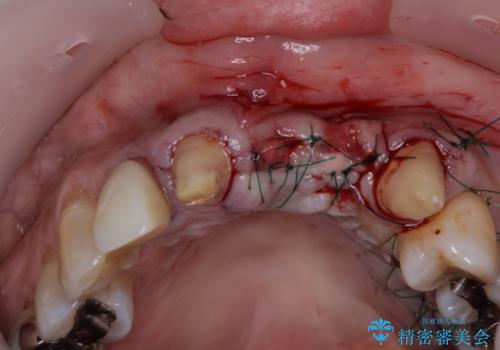

前歯は抜歯が必要であったので、抜歯を行い、その後歯肉移植をおこなった上でオールセラミックブリッジによる補綴治療を行うこととしました。

- 外科手術のため、術後に痛みや腫れ、違和感を伴います

- 外科手術のため、術後に出血、痛みや腫れ、違和感を伴います